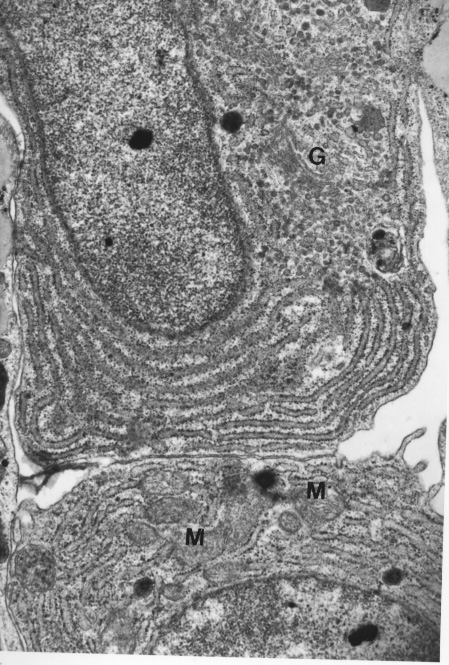

In figure 1 he shows the close relationship of plasma cells and dendritic cells. The dendritic cell is the cell in the middle and the plasma cells are around the edges. You can see the way the plasma cells squeeze themselves against the dendritic cell to maximize the area of the cell exposed to the dendritic cell. They are most likely feeding on viral IL-6 made by the Karposi Sarkoma Herpes virus.

In figure 2 you can see the same thing note that the dendritic cells has no cell extentions because of the fixation methods used in the seventies.